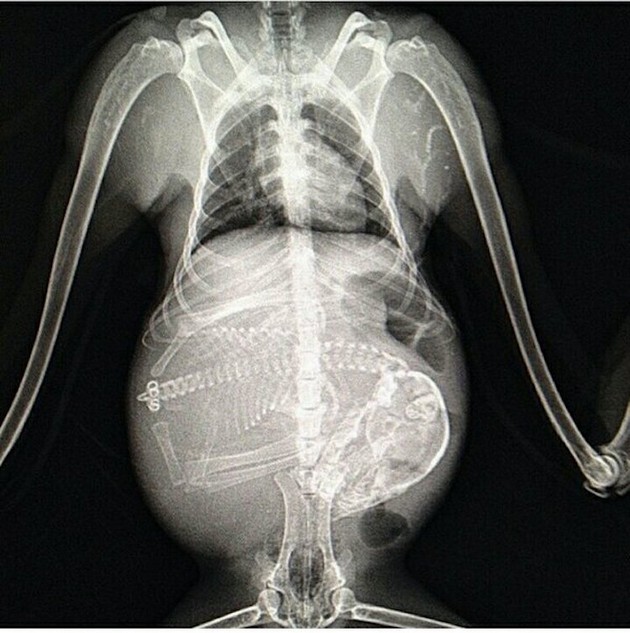

Radostné očakávanie môže u rôznych zvieracích druhov vyzerať všelijako. Fotky, ktoré vám dnes ukážeme sú raritné a rozhodne zaujímavé. Predsa len, videli ste už niekedy tehotné zvieratá cez röntgenové snímky?

Niektoré z nich rodia živé mláďatá, iné zasa kladú vajíčka. Zrod nového života vo zvieracej ríši je každopádne fascinujúci. A ako vyzerajú tehotné zvieratká sa môžete pozrieť na nasledujúcich “lekárskych” snímkoch.

Pes